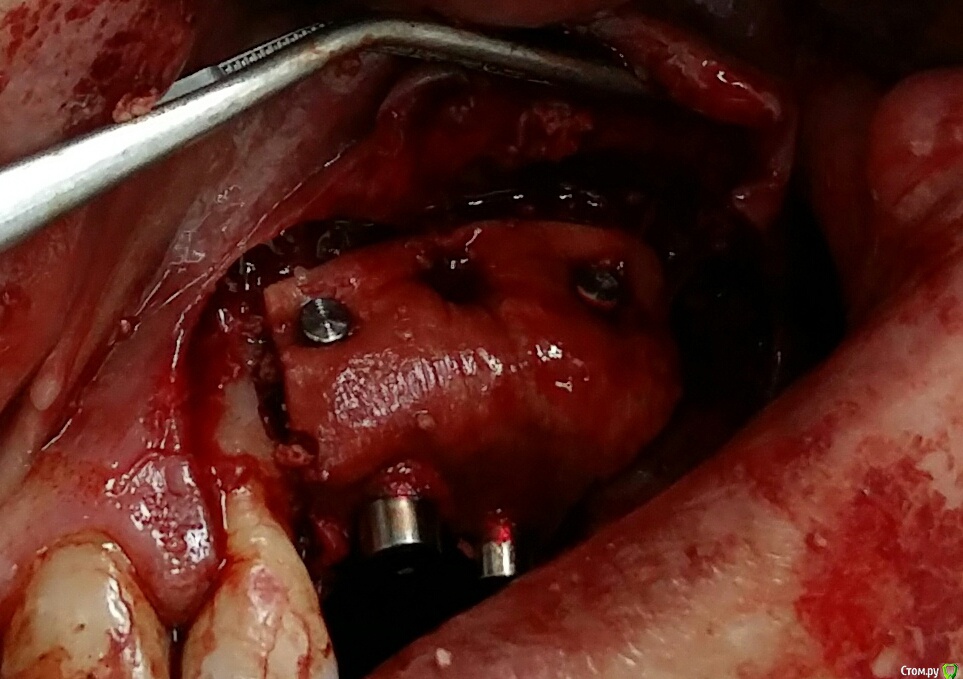

Kostoprav Опубликовано 26 марта, 2017 Поделиться Опубликовано 26 марта, 2017 (изменено) извините за качество фотографт: ауто + биопласт крошка, мембрана еволюшендырка возле 22-ревизия периапикального процесса Изменено 26 марта, 2017 пользователем Kostoprav 3 Ссылка на комментарий